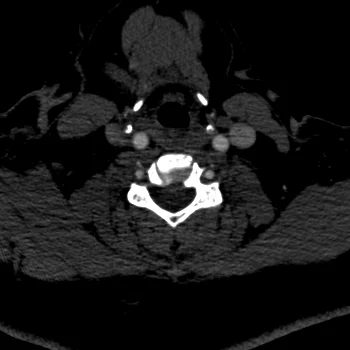

Low contrast dose neck CTA

27 yo F with eGFR of 24 ml/min/1.73m2. Neck CTA requested for concern of vertebral artery dissection. A low-contrast neck CTA performed, with 60% contrast saline mix. A total of 24 mL contrast and 16 mL saline injected at 4.0 mL/sec using power injector. Typical contrast dose for a neck CTA at our institute is about 50 mL.

Conventional CT shows poor enhancement in the carotid and vertebral artery (<200 HU). 40 keV image shows excellent enhancement. No vertebral artery dissection or other abnormality was discovered and patient was discharged.

Conventional CT with poor enhancement